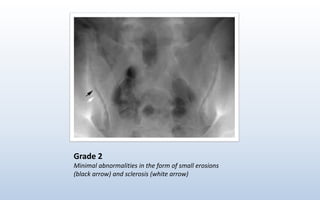

Grade 2

Minimal abnormalities in the form of small erosions

(black arrow) and sclerosis (white arrow)